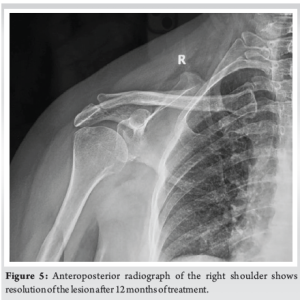

A 20-year-old male presented with pain in the right shoulder region for 2 months. Pain was insidious in onset and dull in nature. Pain was slowly and gradually progressive, aggravating with shoulder movements, but the range of motion was not restricted. He had an occasional lowgrade fever for the past 3 months. There was no history of recent trauma, weight loss, or loss of appetite. There was no past family history of TB. Upon examination, there was no visible fullness over the scapular region. There was tenderness over the spine of the scapula and the adjacent area. No palpable swelling was present. Full range of motion of the shoulder was present, but it was terminally painful. There was no local rise in temperature. There was no hepatosplenomegaly. The plain anteroposterior radiograph of the right scapula revealed a radiolucent, wellfcircumscribed osteolytic lesion at the spine of the scapula with minimal soft tissue involvement (Fig. 1). Other than a raised erythrocyte sedimentation rate (ESR) of 82 mm/h, the rest of the hematological parameters were within normal range. Magnetic resonance imaging (MRI) showed an abnormal marrow signal intensity lesion in the lateral aspect of the spine of the right scapula extending into the proximal acromion process, associated with intraosseous and extraosseous soft tissue, cortical breach, narrow zone of transition, and diffuse surrounding myocutaneous inflammatory changes (Fig. 2). The lesion showed an irregular permeative type of periosteal reaction and a surrounding partially sclerotic rim. A sample was sent from the spine of the scapula for biopsy, and it showed extensive areas of necrosis with numerous discrete epithelioid cell granulomas and Langhan’s giant cells in fibrocollagenous stroma (Fig. 3 and 4). It was consistent with TB, and based on the histopathology report, the patient was treated with four drug antitubercular therapy for 12 months. There was complete resolution both clinically and radiologically at the end of 1.5 years (Fig. 5).

TB of bones and joints is not so uncommon in endemic regions and is associated with significant morbidity. The primary challenge is not the disease pathogenicity itself but the lack of timely diagnosis. After an initial pulmonary infection, TB can involve bones and joints through hematogenous seeding of bacilli. It starts as osteomyelitis in the growth plates of bones, due to its high vascularity, and then spreads to involve the joint [3]. Spine is considered to be the most common site of osteoarticular TB, followed by femur, tibia, and small bones of the hand and feet [4,5,6]. Flat, bone like scapula is a rare site for bony TB. However, in an endemic region such as India, any immunocompetent individual is susceptible to the development of uncommon forms of osteoarticular TB. A patient with scapula TB may present with symptoms of pain over the shoulder, with or without palpable swelling. Initially, tenderness over the affected area can be found. Local rise of temperature and redness are usually not found. Diagnosis is already too late if a discharging sinus is present. The differential diagnosis of these above clinical features includes eosinophilic granuloma, sarcoidosis, metastasis, pyogenic osteomyelitis, and fungal infections [7]. Diagnosis is achieved by being more vigilant toward the symptoms, and the absence of any systemic involvement should also raise suspicion. A thorough clinical examination needs to be done before laboratory and radiological investigations. Markedly raised ESR may assist in diagnosis. Early radiographic images, though not pathognomonic, may show osteolytic lesions with minimal sclerosis with no sequestrum [4,6,8]. MRI, though a useful diagnostic tool, may not be confirmatory, as in this case, MRI showed abnormal marrow signal intensity in the lateral aspect of the spine of the scapula extending to soft tissues and cortical breach. To differentiate TB from other differentials, histopathology is required, which can show epithelioid granuloma as in this case. In the absence of giant sequestrum, most of the osteoarticular TB can be treated with antitubercular therapy alone. An effective multidrug regimen can help in early disease remission [9]. Surgical excision may be required in case of inadequate response to antitubercular treatment for 4–6 weeks or case of giant sequestrum [10]. In the present case, 12 months of antitubercular therapy had completely healed the lesion.